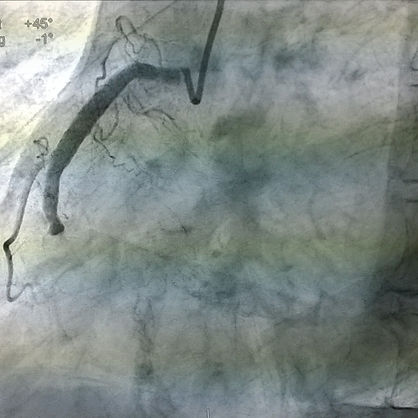

Paso 1.- diagnóstico: en el cual se introduce una guía metálica junto uno o varios catéteres (tubillos de material suave parecido al plástico) muy delgadas (de tamaño aproximado 2-3 milímetros de grosor) a través de las arterias del brazo o de la pierna, hasta el corazón, pintar las arterias del corazón con un medio de contraste especial y a través de "rayos x" visualizar las arterias del corazón, las cuales reciben el nombre de "coronarias" (por su disposición en el corazón en forma de una corona)con esto podemos observar si alguna arteria del corazón está obstruida , por algún coágulo de sangre o por alguna placa de colesterol, lo cual impide que la circulación de la sangre llegue de manera adecuada hasta las células del Corazón, provocando la famosa "angina de pecho" que es el síntoma que precede a un infarto o de manera coloquial una amenaza de infarto del corazón, conocido también como ataque cardiaco, también en los infartos ya establecidos logramos visualizar la o las arterias que se ocluyeron, de esta forma y haciendo un análisis estratégico previo, podremos proseguir al siguiente proceso

Paso 2.- angioplastia coronaria: consiste en introducir a través de las arterias del brazo o de la pierna catéteres suaves y delgados (2-3 mm) así como guías metálicas tan delgadas como un cabello, con las cuales se llega hasta la obstrucción de las arterias del corazón se atraviesan de manera muy delicada y cuidadosa, si se logra, se avanza un globo de material especial desinflado y a nivel de la obstrucción de las arterias coronarias se infla a diferentes presiones hasta lograr compactar el coágulo o placa de colesterol alrededor de las paredes de la arteria afectada liberando de esta forma la circulación con lo mejora del flujo de sangre hasta las células del corazón, mejorando su funcionamiento y evitando un infarto en los pacientes en los que se evidencia a través de algún estudio isquemia miocárdica (que significa sufrimiento del tejido del corazón por disminución en el aporte del flujo sanguíneo, oxígeno y otros nutrientes de la sangre o que el aumento de la necesidad de este flujo sanguíneo, ejemplo ejercicio o estrés emocional, empeore el sufrimiento de las células del músculo cardíaco) actualmente además de destapar literalmente las arterias con este globo se implanta un dispositivo llamado stent el cual es una malla metálica que se impacta por dentro de las arterias a nivel de la obstrucción por placas de colesterol o coágulos de sangre, impidiendo que la arteria se vuelva a cerrar durante varios años este dispositivo se creó especialmente para permanecer dentro de las arterias durante toda la vida del individuo, mejorando el pronóstico de vida y la calidad de vida del paciente